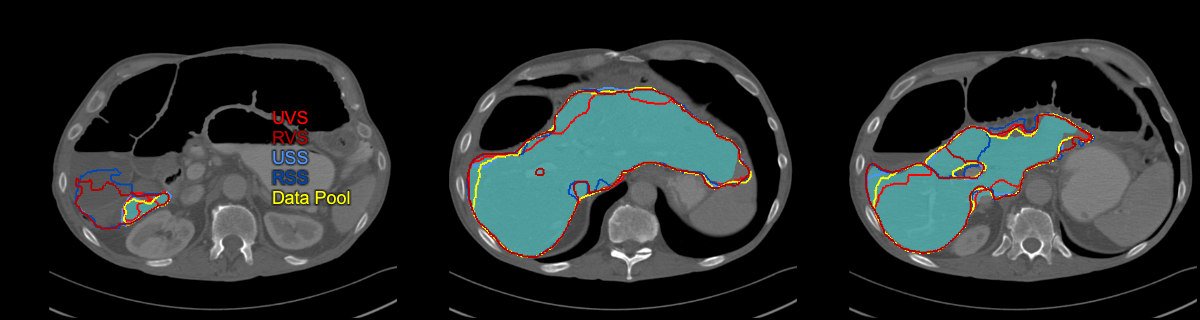

Refer to caption

(a) Polycystic liver case where the USS strategy resulted in the best segmentation: UVS 0.83 Dice, 25.2% RVE, 8.0 mm MSD, 64 mm HD; RVS 0.53, 63.2%, 18.0 mm, 64 mm; USS 0.94, 5.2%, 3.2 mm, 59 mm; RSS 0.84, 21.7%, 8.7 mm, 65 mm; Data Pool 0.85, 24%, 8.3 mm, 64 mm.

(b) Case where UVS outperformed all models: UVS 0.96 Dice, 0.4% RVE, 1.1 mm MSD, 17 mm HD; RVS 0.96, 3.1%, 1.4 mm, 21 mm; USS 0.94, 5.6%, 1.5 mm, 24 mm; RSS 0.95, 2.5%, 1.4 mm, 22 mm; Data Pool 0.93, 9.1%, 2.1 mm, 32 mm.

(c) Case where both random strategies resulted in overestimation in the caudal liver region: UVS 0.91 Dice, 6.1% RVE, 2.4 mm MSD, 23 mm HD; RVS 0.93, 3.4%, 2.1 mm, 25 mm; USS 0.95, 1.0%, 1.5 mm, 17 mm; RSS 0.77, 41.0%, 23.3 mm, 141 mm; Data Pool 0.94, 0.2%, 1.7 mm, 21 mm.

(d) Case for which all strategies except RVS achieved very good segmentation performance: UVS 0.97 Dice, 0.1% RVE, 0.9 mm MSD, 18 mm HD; RVS 0.91, 11.8%, 2.9 mm, 36 mm; USS 0.96, 1.8%, 1.0 mm, 20 mm; RSS 0.97, 1.6%, 0.9 mm, 20 mm; Data Pool 0.97, 0.0%, 0.8 mm, 20 mm.

Figure 3: Representative examples presenting segmentation output of the converged models and the model trained on the whole data pool.

In our work, we proposed the uncertainty slice sampling (USS) strategy in the context of pool-based active learning. Our strategy selects 2D image slices from a pool of 3D volumes using aggregated voxel-wise predictive entropy as the uncertainty measure. We evaluated the proposed strategy on a CT liver segmentation task and compared it with random slice sampling (RSS), uncertainty volume sampling (UVS), and random volume sampling (RVS) strategies. The model trained using the USS data (4% of available data) achieved significantly better results than the remaining strategies. Although after five active learning iterations the USS model was inferior in performance on average to the model trained on all available data, it provided more robust segmentation as measured by 5th DICE and 95th MSD metrics. We hypothesize that this can be attributed to differences in the training set composition. The training set resulting from the USS contains a bigger proportion of difficult/rare cases compared to the whole data-pool training set, which effectively causes that the model sees them more frequently during the training process. Fig. 3 shows exemplary outputs from the investigated models including two hard cases from the test set: a polycystic (Fig. 3(a)) and a resected (Fig. 3(b)) liver. We think that the robustness of the whole data pool model could be increased by employing a hard example mining during training to dynamically adjust the sampling rate of difficult examples[26, 27]. Selecting only uncertain cases in the course of active learning can overload the model with difficult examples causing a performance drop. This can be observed for the USS strategy after the first iteration (see Fig. 1, where the model performs substantially worse than its random counterpart (RSS).